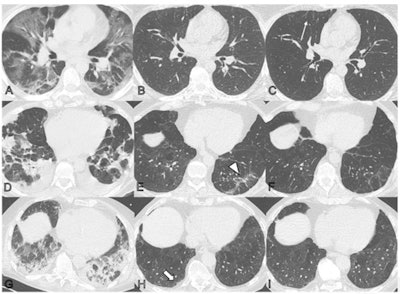

Luger's group conducted a study that included 91 patients evaluated with chest CT after contracting COVID-19 pneumonia at two, three, six, and 12 months after symptom onset. Of these, 49 (54%) showed abnormalities on chest CT at the one-year mark. CT exam findings were graded by lung lobe using a severity score that ranged from 0 (normal) to 25 (all lobes involved).

- Common abnormal findings were subtle subpleural reticulation, ground-glass opacities, or both (34%); 20% of the abnormal CT exams showed extensive ground-glass opacities, reticulations, bronchial dilation, or microcystic changes.